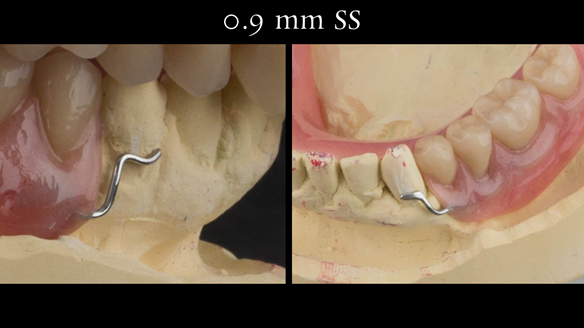

This newsletter describes in step by step detail the transition from acrylic based immediate dentures to metal based definitive dentures.

- Definitive dentures (Mk 2) – complete upper metal reinforced and lower cobalt chromium based partial of hygienic Scandinavian design to be made 9 - 12 months after extractions of all upper teeth and LR5 and LL4